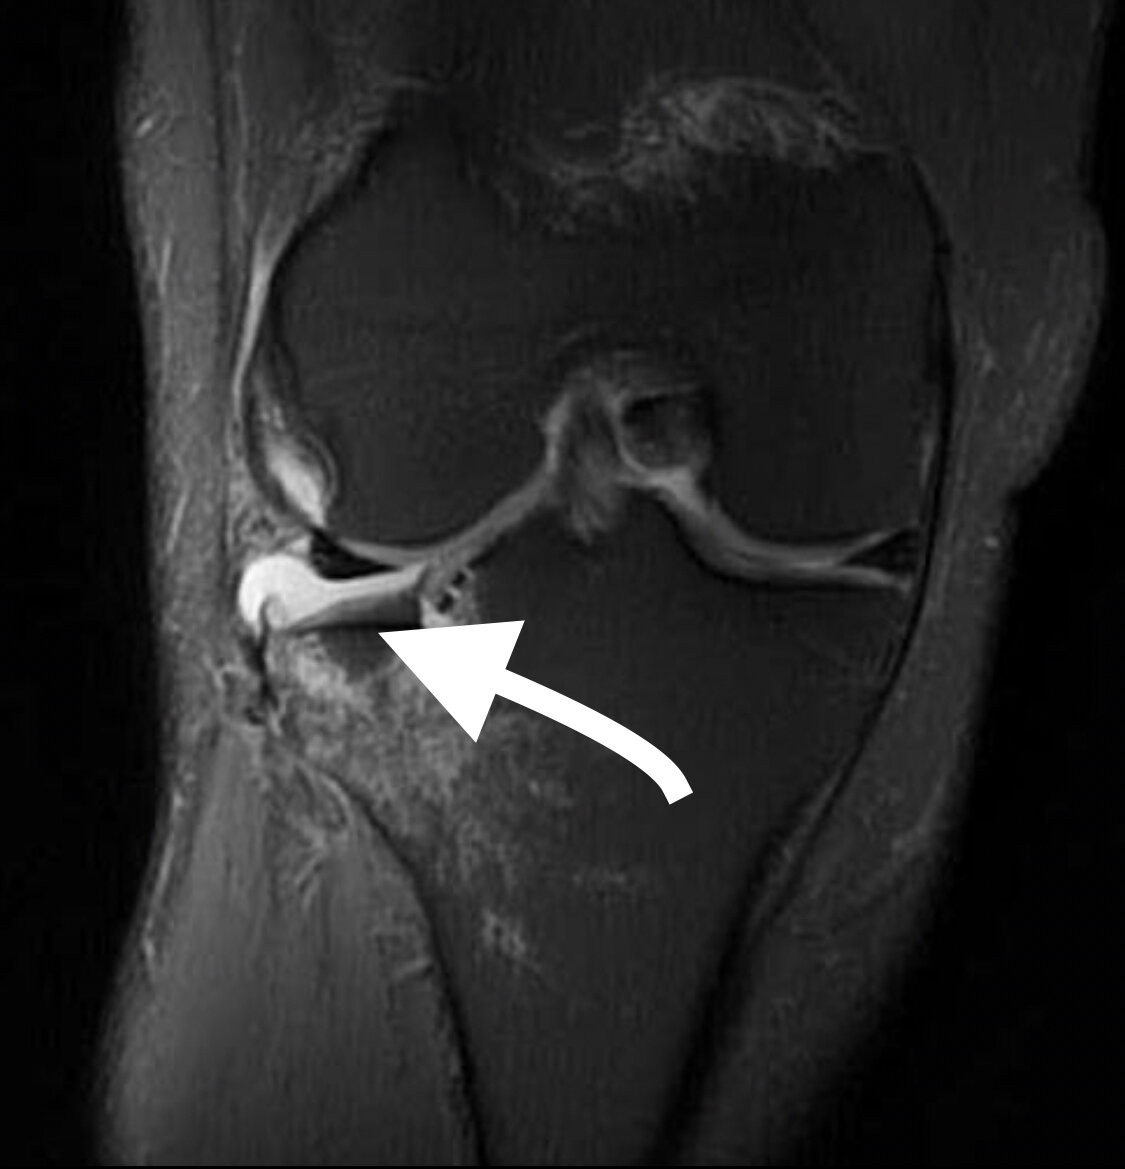

Мужчина 31 год, травма на горных лыжах. Разрыв передней крестообразной связки, повреждение и экструзия медиального мениска, повреждение латерального мениска «плавающий мениск».